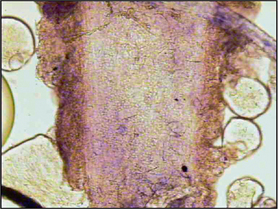

Direct microscopy: Most dermatophytosis cases in domestic animals involve ectothrix invasion of hair shafts by fungal spores which can be visualized under ×40 magnification using the light microscope. Fluorescing hairs or hairs from lesions may be plucked for direct microscopic examination. Samples should be mounted on the slide in liquid paraffin or potassium hydroxide. Hair shafts with distorted or damaged cuticles should be examined under higher power for the presence of fungal spores (Fig. 2.4). Although a test with high specificity in the right hands, this is not a sensitive technique for the diagnosis of dermatophytosis in the hands of the inexperienced clinician.

image

Figure 2.4 Hair shaft infected with dermatophytes.

(Courtesy of Dr N. McEwan.)